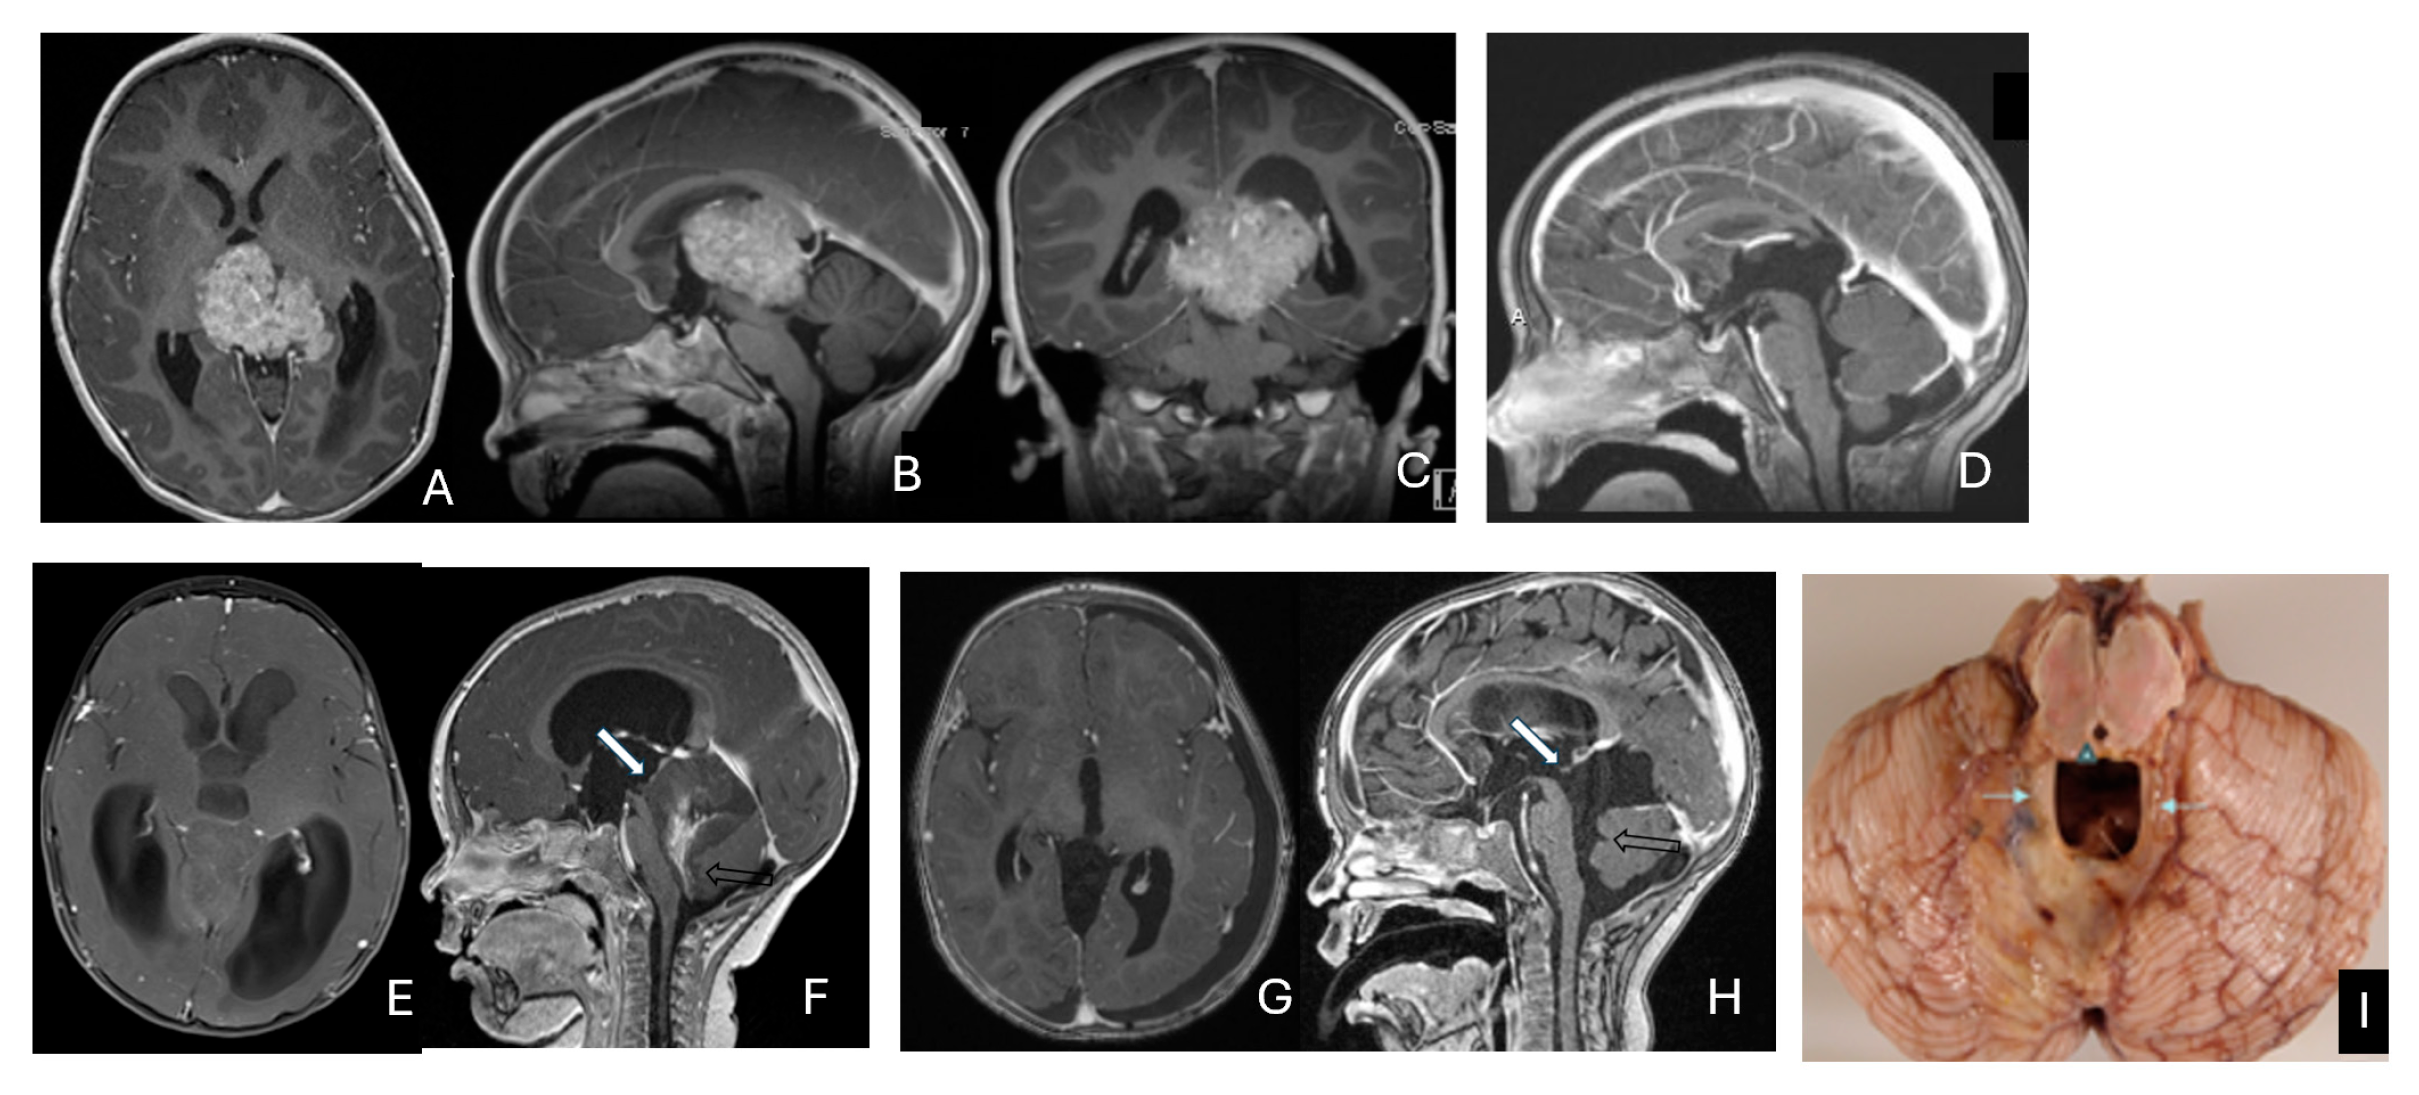

Tumor epicenters and patterns of extension were best delineated by operative observations combined with preoperative and postoperative imaging (Figure 1). Three patients had tumors involving both the temporal and frontal lobes that crossed the Sylvian fissure (Figure 2). Despite appearance of thalamic involvement on preoperative imaging, two patients had tumors primarily occurred in the basal ganglia, which became more evident on postoperative MRI (Figure 3). Additional hemispheric tumor extended into the thalamus. These lesions were resected via a trans-sylvian approach.

Figure 1.

Cerebral lobar ATRT. (A–D): 20-month-old boy with a parietal intraparenchymal ATRT. Preoperative axial images (A,B) and postoperative axial (C) and coronal (D) images confirm the intraparenchymal location following resection. (E–H): 26-month-old boy with a large heterogeneous frontal mass with multiple peritumoral cysts. Preoperative axial (E) and coronal (F) images, and postoperative axial (G) and coronal (H) images after gross-total resection support a frontal lobe origin despite of the basal ganglia origine as the preoperative imaging suggetsed.

Figure 2.

Multi-lobe ATRT. (A–D): A 3-year-old boy with a heterogeneous frontotemporal ATRT with encasement of Sylvian vessels on MR images ((A), axial; (B), coronal). Intraoperatively, the tumor replaced both the frontal and temporal opercula, extended to the anterior, and displaced/encased branches of the middle cerebral artery. Postoperative MR images after resection ((C), axial; (D), coronal) confirm multilobe involvements. (E–H): of a 30-month-old boy with a temporoparietal cystic ATRT crossing the Sylvian fissure shown on T2-weighted MR images ((E), axial; (F), coronal). Correlative intraoperative findings and imaging demonstrated the tumor extending from the temporal lobe into the posterior frontal lobe across the Sylvian fissure and encasing middle cerebral artery branch. Post-resection MR images ((G), axial; (H), coronal) show a resection cavity spanning the temporal and posterior frontal opercula.

Figure 3.

Basal ganglia ATRT. (A–D): Post contrast MR images ((A)-axial, (B)-coronal) of 13-month-old boy with deep seated ATRT. Note the solid tumor with peritumoral cysts at the basal ganglia with one cyst extending to the thalamus. Post-resection MR images ((C)-axial, ((D)-coronal) show the tumor resected cavity in the basal ganglia with the thalamus clear of tumor involvement. (E–H): Post contrast MR images ((E)-axial, (F)-coronal) of a 23-month-old boy with a large ATRT of deep temporal lobe and the insula extending to the basal ganglia. The tumor was predominantly in the basal ganglia as shown postoperative MR ((G)-axial, (H)-coronal).

Three tumors were predominantly located within the ventricle, two within the lateral ventricle and another within the third ventricle (Figure 4). None appeared to arise from the choroid plexus or as pedunculated lesions from the ependymal layer; rather, operative and imaging features supported a paraventricular origin because of diffuse attachment to the ventricular wall. Two large hemorrhagic hemispheric tumors extended into the lateral ventricle. These paraventricular ATRT extends into the lateral ventricle (Figure 5).

Figure 4.

Intraventricular ATRT. (A–D): A 7-month-old boy with ATRT within the left lateral ventricle with associated hydrocephalus shown on MR images ((A), axial; (B), coronal; (C), sagittal). Note irregular peritumoral cysts and ependymal invasion which was confirmed at surgery. Postoperative MR image ((D), axial) shows a gross-total resection. The patient had a history of rhabdoid tumor predisposition syndrome. (E–H): A 34-month-old boy with MR images ((E), axial; (F), coronal; (G), sagittal) showing an intraventricular mass at the anterior horn based on the septum pellucidum. ATRT was originated at the junction of the septum pellucidum. Post-contrast MR ((H), axial) confirms resection. (I–L): Post-contrast MR images ((I), axial; (J), coronal; (K), sagittal) of a 3.5-year-old boy demonstrate a large, enhancing third ventricular ATRT with partial extension into the lateral ventricle. The lesion was removed via an interhemispheric transcallosal approach ((L), sagittal).

Figure 5.

Paraventricular ATRT with ventricular extension. (A–D): A 3-month-old girl who presented with emesis followed by acute decerebrate posturing. Post-contrast MR images ((A), axial; (B), coronal; (C), sagittal) reveal a large hemorrhagic mass in a deep centrencephalic location. Postoperative MR ((D), axial) shows a focal dilation of the lateral ventricle after subtotal resection of a parietal para-ventricular ATRT.

Three patients presented with massive subdural/parenchymal masses involving both cerebral hemispheres across the falx cerebri; two bi-frontal and one in bi-occipital (Figure 6). These tumors appeared to originate within the cerebral hemispheres and permeate or traverse the falx cerebri, resulting in bilateral disease.

Figure 6.

Bi-hemispheric ATRT. (A–E): MR images ((A), axial; (B), coronal; (C), sagittal) of a 4-year-old boy show a bifrontal ATRT crossing the falx cerebri, with heterogeneous enhancement. The corpus callosum is compressed posteriorly. At surgery, left frontal component invades and permeates through the falx with extension into the right subdural space. Postoperative images after bifrontal craniotomy ((D), axial; (E), coronal) show tumor resection. Bi-occipital hemispheric ATRT. (F–J): MR images ((F,G), axial; (H), coronal) of a reveal a 22-month-old girl large, inhomogeneous left occipital lobe mass crossing the midline into the right occipital lobe. The lesion invades the posterior falx cerebri and extends into the medial occipital lobe of the right side. A highly vascular tumor was resected via a left occipital craniotomy; the right occipital component was not removed with concern of blindness due to preexisting right homonymous hemianopia. She received chemoradiation with durable disease resolution for over 15 years, as shown on follow-up post-contrast MR ((I), axial; (J), coronal).